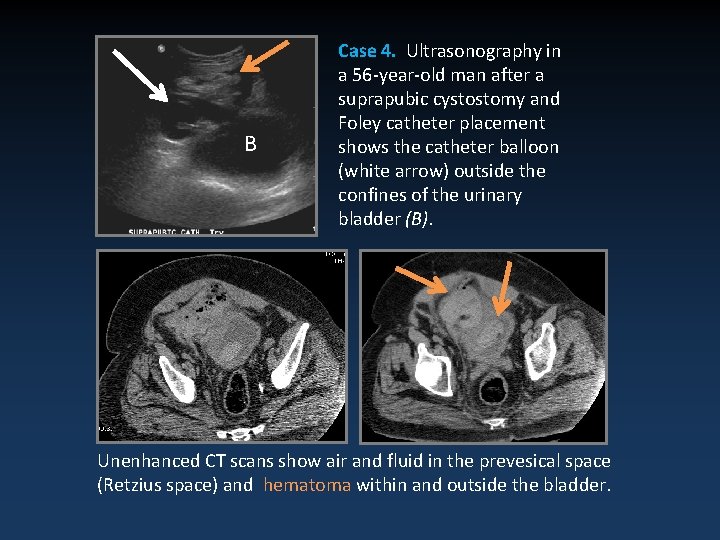

B Case 4. Ultrasonography in a 56 -year-old man after a suprapubic cystostomy and Foley catheter placement shows the catheter balloon (white arrow) outside the confines of the urinary bladder (B). Unenhanced CT scans show air and fluid in the prevesical space (Retzius space) and hematoma within and outside the bladder.